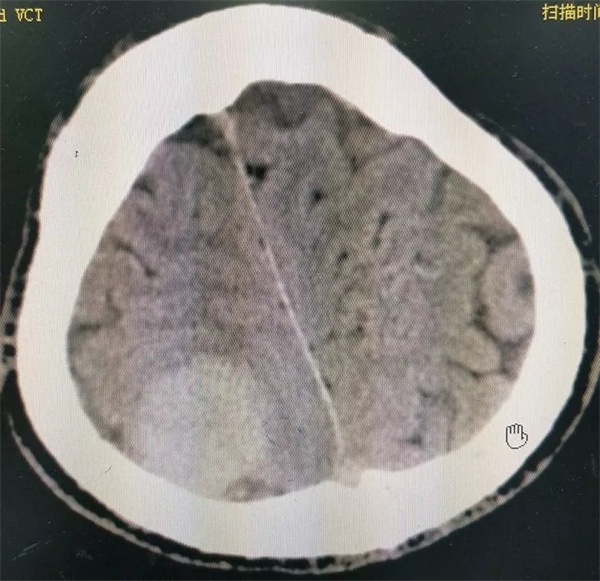

11月28日凌晨一点左右,朱某睡眠正酣,突发四肢抽搐,口吐白沫,双眼上翻,呼之不应,持续数分钟方才停止,睡在一旁的妻子目睹这一切,仿佛经历晴天霹雳,还以为丈夫“被鬼打了” 或“是中邪了”,一时间不知所措。待缓过神后还是拨打120,120把朱某送至捕鱼游戏 神经外科,头颅CT 检查提示右侧顶枕叶类圆形高密度占位,接诊医师姚勇、李世清考虑颅内占位所致继发性癫痫。